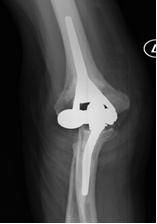

1) Protesi totale di gomito: riproduce la superficie articolare del gomito mediante due componenti, una omerale e l’altra ulnare (Fig. 3). L’accoppiamento tra le componenti protesiche che scorrono tra loro durante il movimento del gomito è metallo-polietilene. A seconda della presenza o meno di una cerniera -che crea un vincolo meccanico tra la componente omerale ed ulnare- le protesi totali di gomito si dividono in:

- con cerniera (linked): modelli che presentano una stabilità intrinseca e consentono un più ampio spettro di indicazioni (Fig. 3). Attualmente tali modelli sono i più comunemente utilizzati in Italia e Stati Uniti.